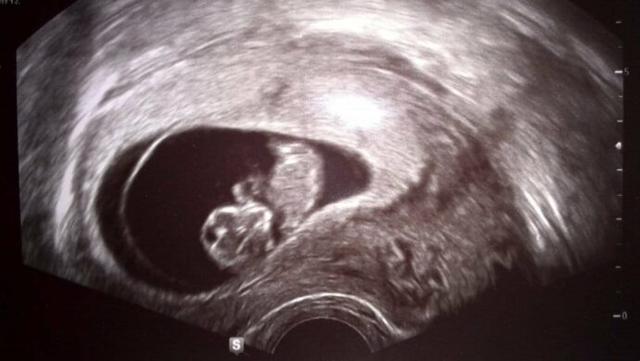

Im ersten Trimester der Schwangerschaft, genauer gesagt ab der 5. Woche, beginnt das Herz des Embryos zu schlagen. Dieser Herzschlag kann bereits ab der 6. Woche im Ultraschall sichtbar gemacht werden. Der Arzt kann die Herztöne des Babys hören und auf dem Bildschirm des Ultraschallgeräts sehen. Der Herzschlag ist ein wichtiger Meilenstein in der Entwicklung des Embryos und ein Zeichen dafür, dass alles gut verläuft. Es ist ein bewegender Moment für die werdenden Eltern, den Herzschlag ihres Kindes zum ersten Mal zu hören oder zu sehen.

Der Herzschlag im Ultraschall wird als Hinweis auf eine intakte Schwangerschaft betrachtet und gibt den Ärzten und Eltern Sicherheit über das Wohlbefinden des Babys. Es ist wichtig zu beachten, dass der Zeitpunkt des ersten Nachweises des Herzschlags im Ultraschall von verschiedenen Faktoren abhängen kann, wie zum Beispiel von der Position des Embryos und der Qualität des verwendeten Ultraschallgeräts.

Im ersten Schwangerschaftsdrittel, genauer gesagt ab der 6. Woche, ist der Herzschlag des Embryos bereits auf dem Ultraschall sichtbar. Dies ist ein wichtiger Meilenstein in der Entwicklung des Fetus und ein erster Hinweis darauf, dass alles gut verläuft. Der Herzschlag kann dann auch regelmäßig überprüft werden, um sicherzustellen, dass das Kind sich normal entwickelt.

Im ersten Drittel der Schwangerschaft, genauer gesagt ab dem 22. Tag oder in der 5. Schwangerschaftswoche (SSW), beginnt das Herz des Embryos zu schlagen. Dieser Herzschlag kann bereits ab der 6. Woche mithilfe eines Ultraschalls nachgewiesen werden. Zu diesem Zeitpunkt ist der Fetus etwa 6 cm lang und wiegt rund 15g.

Der Herzschlag des Fetus kann ab der 5. Schwangerschaftswoche (SSW) im Ultraschall festgestellt werden. In dieser Zeit beginnt das Herz zu schlagen und der Herzschlag ist bereits ab der 6. Woche auf dem Ultraschall sichtbar. Der Herzschlag wird als ein wichtiger Meilenstein in der frühen Schwangerschaft angesehen, da er darauf hinweist, dass die Entwicklung des Embryos gut verläuft.

– Der Herzschlag kann mit Hilfe eines vaginalen Ultraschalls oder eines Bauchultraschalls festgestellt werden.